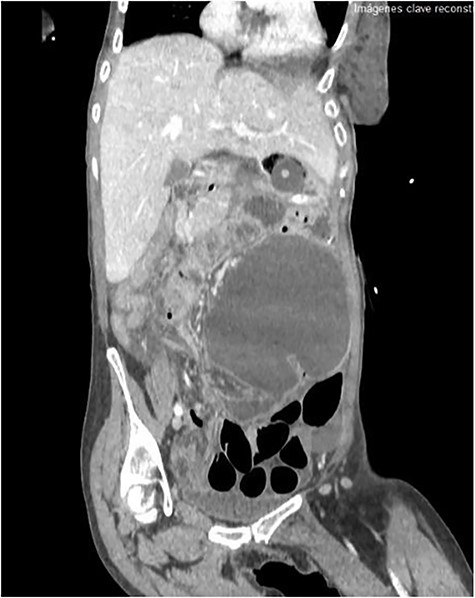

The emergency blood test showed a normochromic and normocytic anemia with an hemoglobin of 10.1 mg/dl and a leukocytosis of 11.150/ul with 70% neutrophils. The abdominal radiography showed a prominent dilation of a small bowel loop. The CT scan reported an 18-cm dilated loop. The main diagnostic suspicion was a small bowel volvulus without signs of ischemia or perforation (Figs 1–3).

With this diagnosis, an emergency laparotomy is performed. It showed a cecum volvulus that compromised 6 cm of distal ileum. The cecum was ischemic, with transmural necrosis. Ileocechectomy was performed including a 15-cm segment of distal ileum. Intestinal transit was reconstructed with mechanical latero-lateral ileo-colic anastomosis with manual reinforcement. The closure of the abdominal wall was performed with a supraaponeurotic prophylactic mesh.